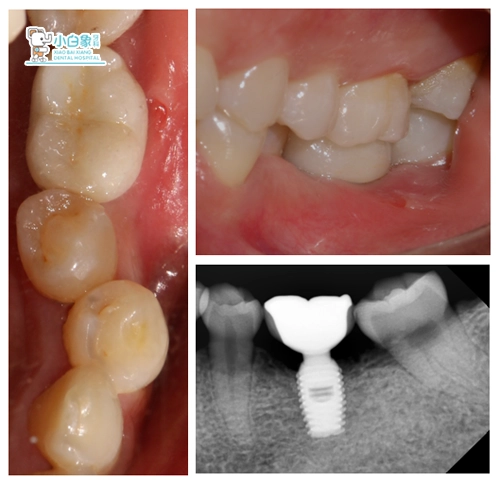

2018年2月1日 戴牙

十天后复查